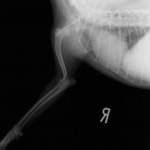

■ミニチュアダックスフント 1歳 去勢オス

前肢の成長板早期閉鎖、前肢の重度の外反変形が認められました。

関節面の変形が重度に認められます。